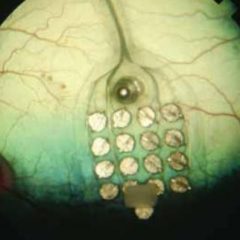

A Shamir tem vindo a desenvolver parcerias e atividades de carisma social, com vista a ajudar quem mais precisa. No âmbito de mais um protocolo estabelecido, desta feita com a Junta de Freguesia de Paranhos, no Porto, ao qual também se associou o Hospital de S. João nas consultas de oftalmologia, foram oferecidos conjuntos de […]